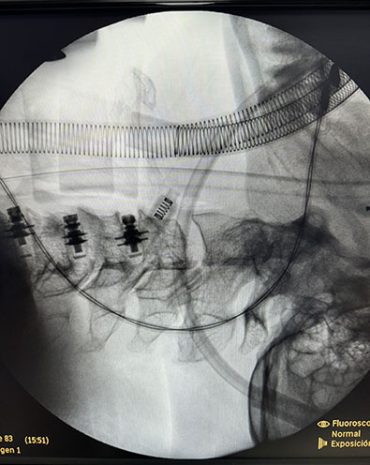

Cirugía Convencional:

Incisiones de diferentes medidas. Se abordan patologías degenerativas, tumorales o infecciosa, traumática.

Cirugía Mínima Invasión:

Percutánea:

Incisiones muy pequeñas, y menor manipulación del tejido muscular adyacente.

• Luxaciones craneocervicales

• Fracturas de columna cervical, dorsal o lumbar

• Hernias de disco cervical, dorsal o lumbar

• Enfermedad degenerativa de la columna cervical

• Dolor radicular cervical, dorsal o lumbar

• Dolor cervical, dorsal o lumbar (ciática)